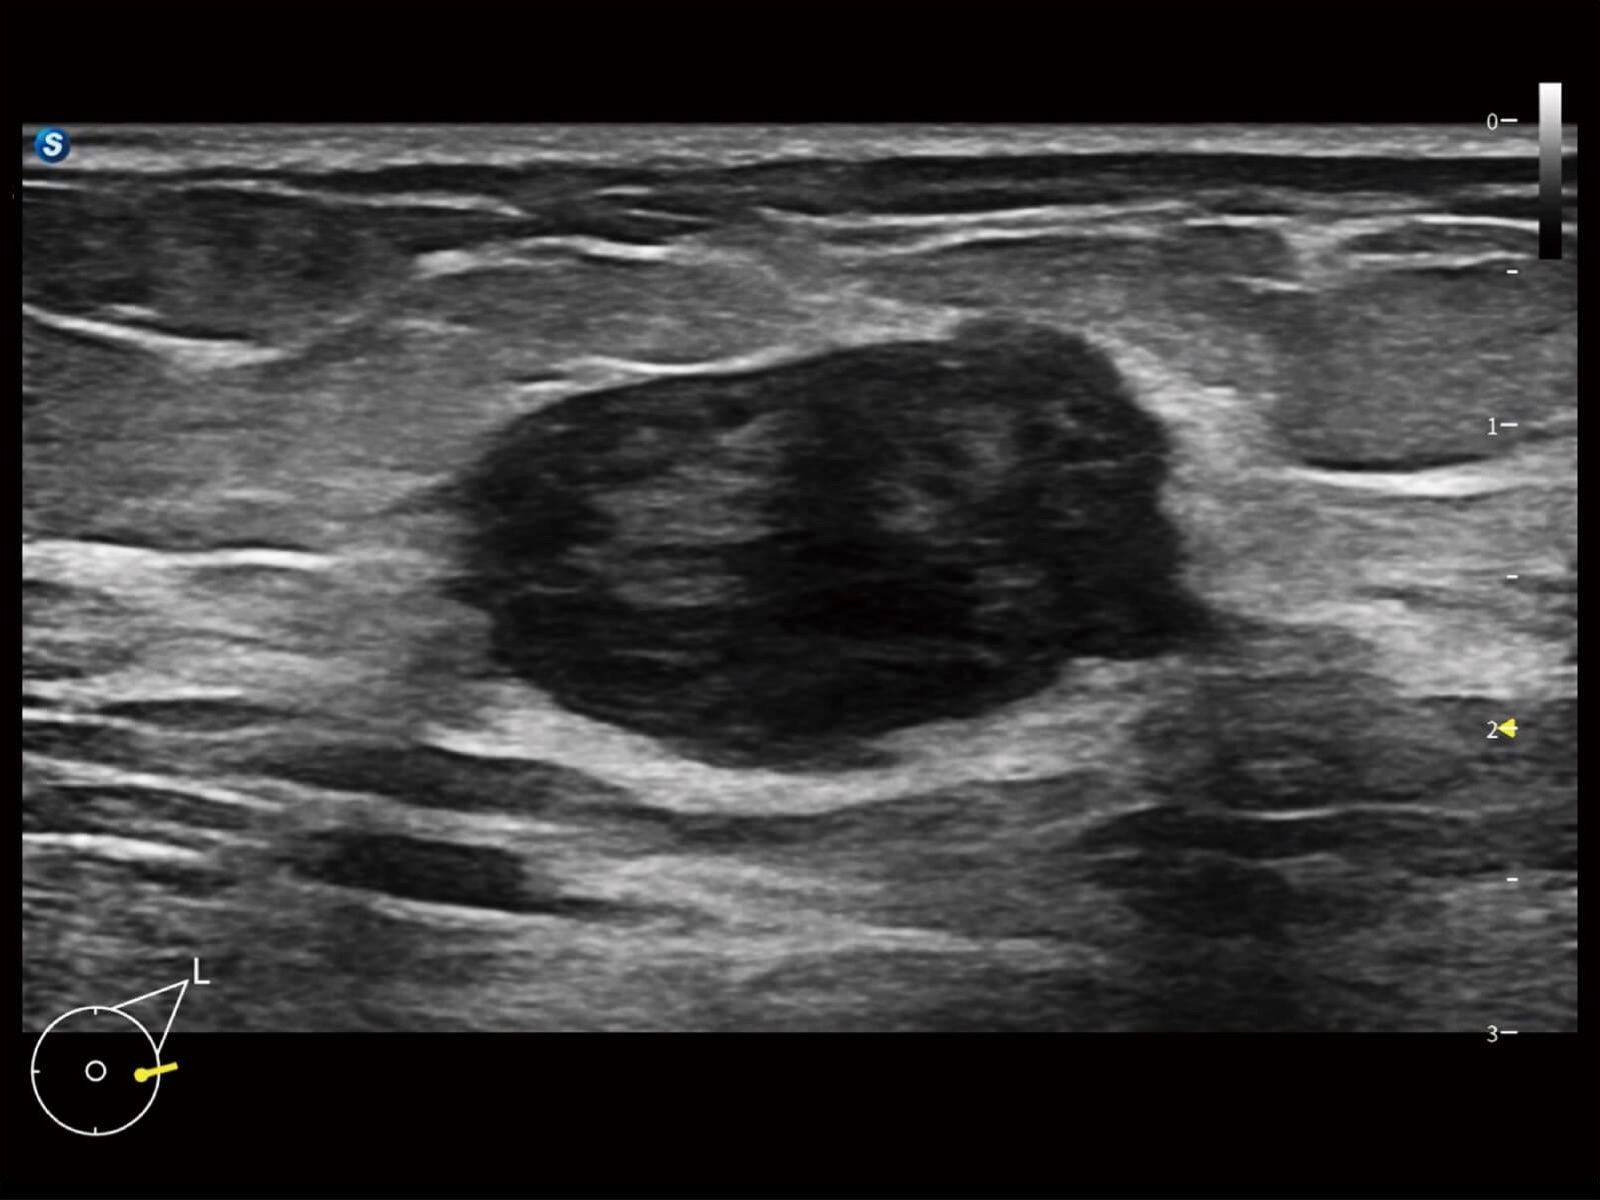

全身应用

妇产应用

专科应用